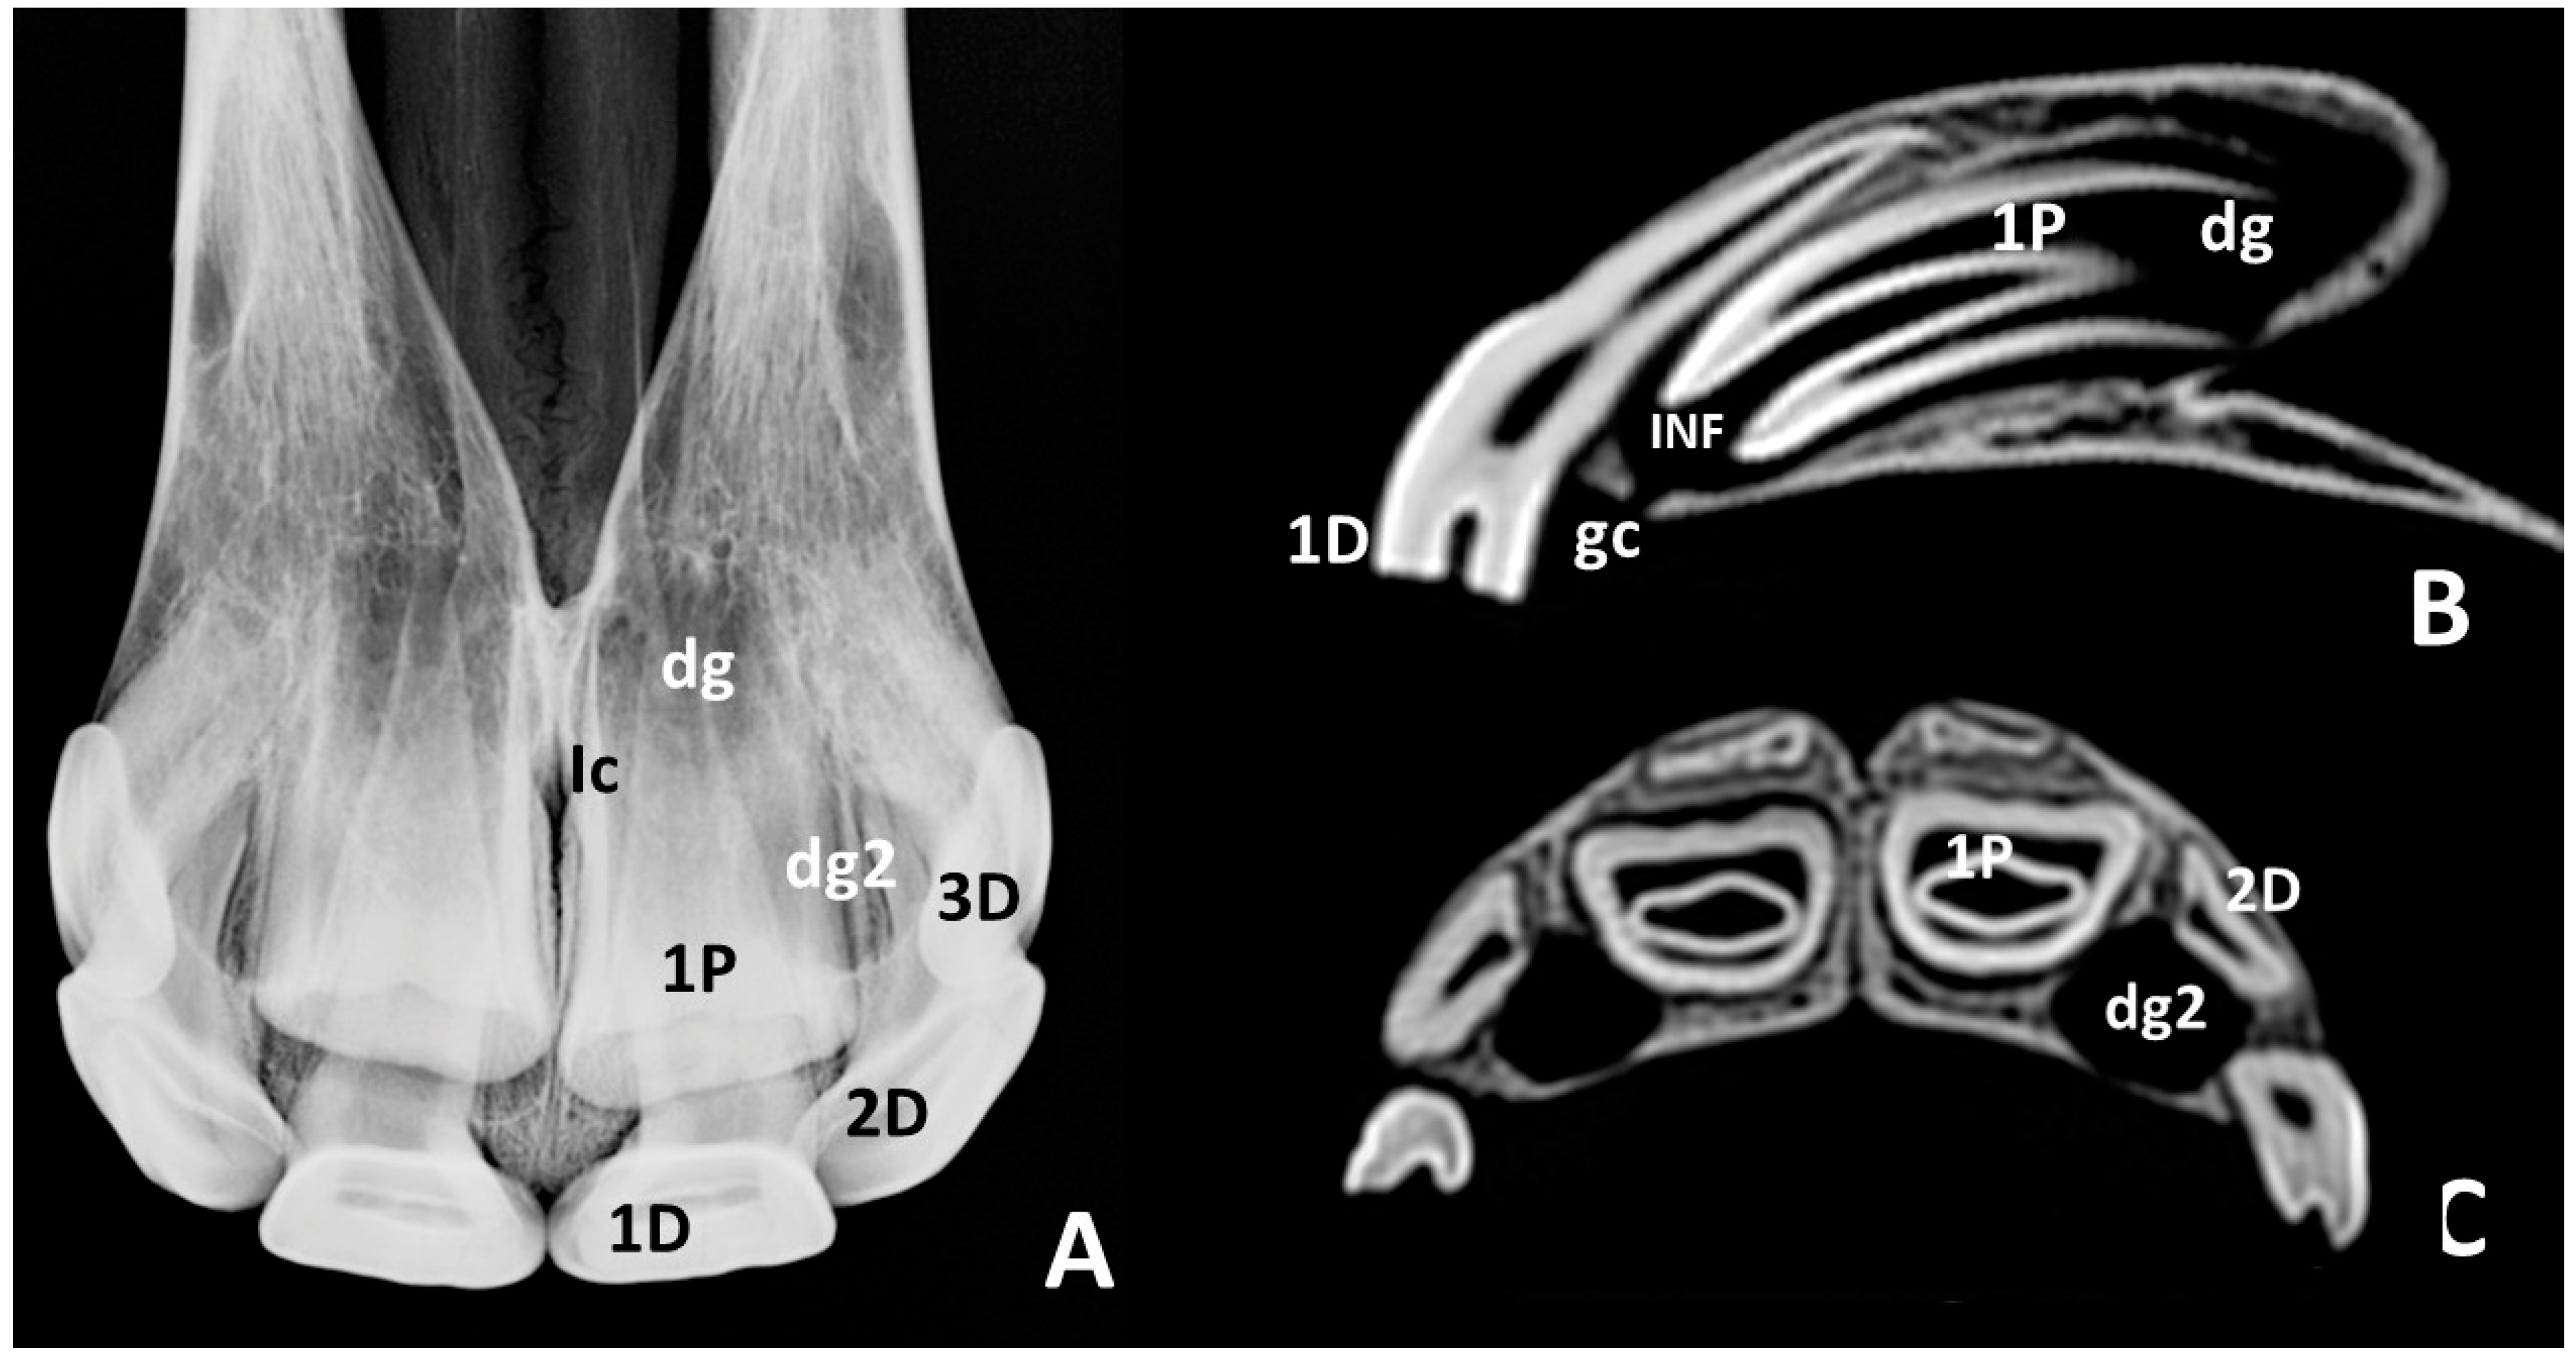

3.2. Radiographic and CT Studies

4.1. Deciduous Incisors: Radiographic and CT Studies

4.2. Permanent Incisors and Alveoli: Radiographic and CT Studies